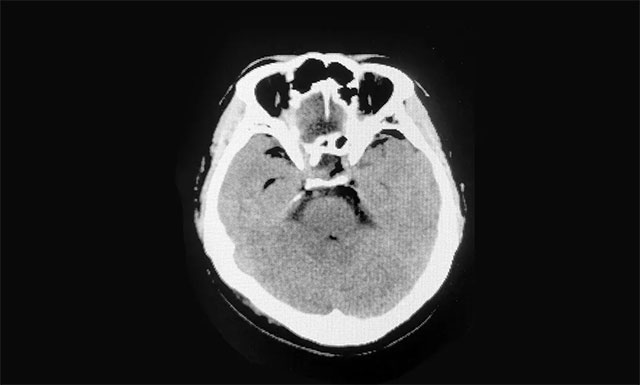

▲ 术后影像显示肿瘤被切除